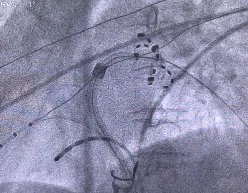

术中心电生理团队详细分析了患者异常解剖结构,克服解剖困难,完成镜向房间隔穿刺。在Ensite三维导航下使用Farapulse脉冲导管进行左房建模,针对镜像反位的肺静脉,术者调整至“镜面操作模式”,精准完成左右肺静脉异常电位隔离。结合本中心前期研究数据,根据消融过程中肌颤强弱的部位顺序,团队采用独特的消融顺序:左下肺静脉→左上肺静脉→右下肺静脉→右上肺静脉→上腔静脉,从而减少镇静药物用量,提高手术效率,降低镇静镇痛药物风险。核心消融过程仅用时20分钟,共放电41次,单次放电2.5秒。术后反复行左房刺激,均未诱发房颤、房扑及室上速,手术精准成功。

房间隔穿刺(左1左2)及肺静脉消融(右1:左下网篮状消融;右2:右下花瓣状消融)